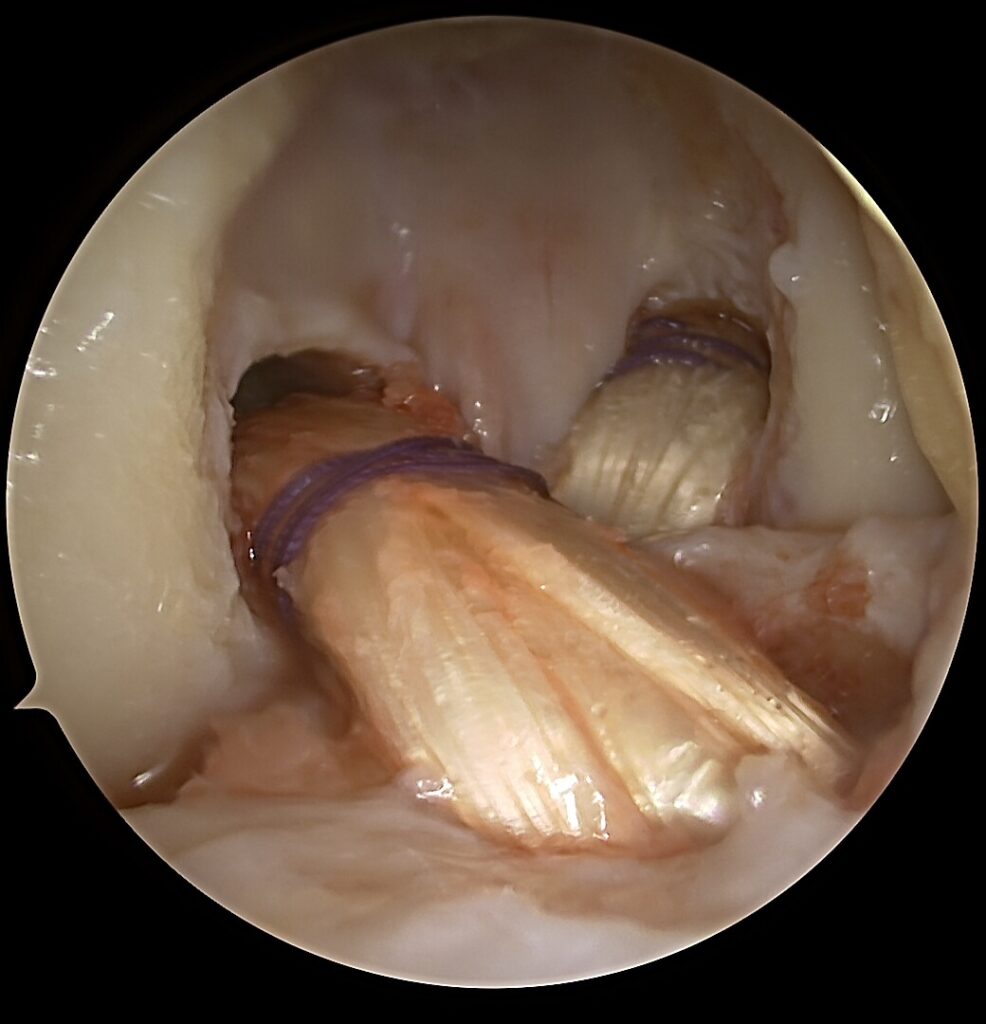

Kodėl V formos rekonstrukcija?

anatomiškai atkuria dvi funkcines kelio stabilumo kryptis

✔️ geriau paskirsto apkrovas

✔️ mažina likutinio nestabilumo riziką

Ši technika ypač svarbi po blauzdos kaulų išnirimo, kai pažeidžiamos kelios vidinės struktūros vienu metu.